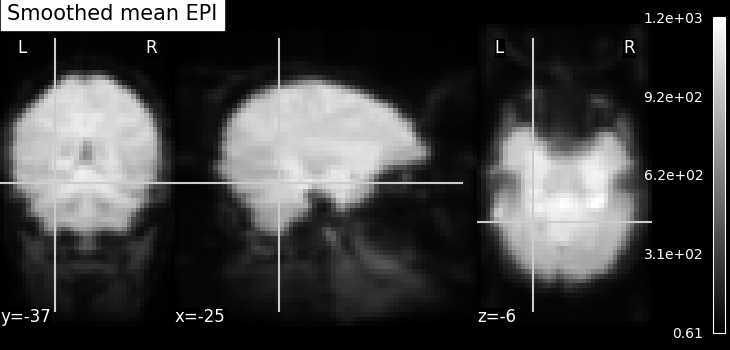

Smoothing: Functional MRI data have a low signal-to-noise ratio.

When using methods that are not robust to noise, it is useful to apply a

spatial filtering kernel on the data. Such data smoothing is usually applied

using a Gaussian function with 4mm to 12mm

full-width at half-maximum (this is where the FWHM

comes from). The function smooth_img accounts for

potential anisotropy in the image affine (i.e., non-indentical

voxel size in all the three dimensions). Analogous to the

majority of nilearn functions, smooth_img can

also use file names as input parameters.

fmri_img = image.smooth_img(fmri_filename, fwhm=6)

mean_img = image.mean_img(fmri_img, copy_header=True)

plot_epi(mean_img, title="Smoothed mean EPI", cut_coords=cut_coords)